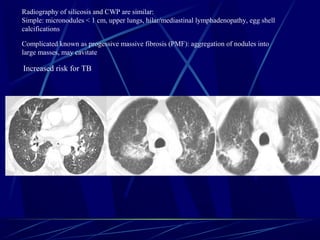

Radiography of silicosis and CWP are similar:

Simple: micronodules < 1 cm, upper lungs, hilar/mediastinal lymphadenopathy, egg shell

calcifications

Complicated known as progessive massive fibrosis (PMF): aggregation of nodules into

large masses, may cavitate

Increased risk for TB